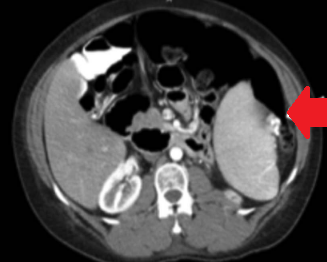

Endoscopic image after performance of splenectomy. Complete disappearance of the varices of the fundus of the stomach (Courtesy Dr. V. Penopoulos)

Abdominal CT scan. Visible presence of varices at the hilum of the spleen (Courtesy Dr. V. Penopoulos)